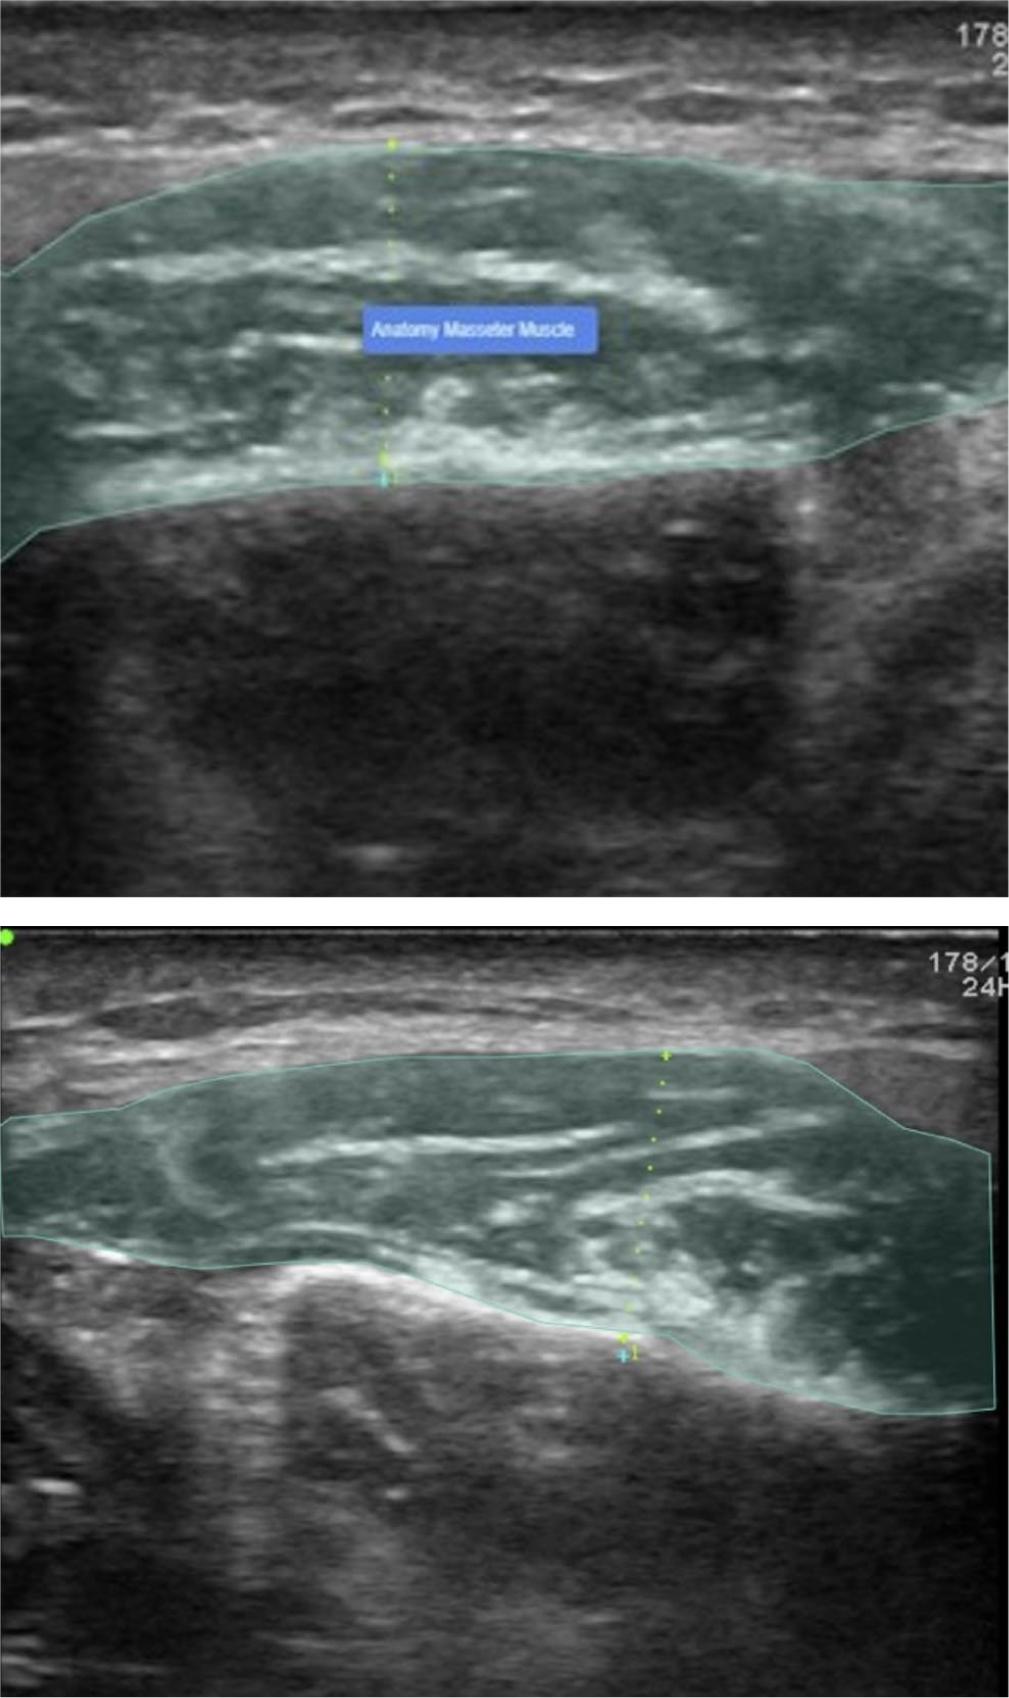

Fig. 1.

Fig. 2.

Evaluation for diagnostic performance by AI model set for masseter muscle segmentation